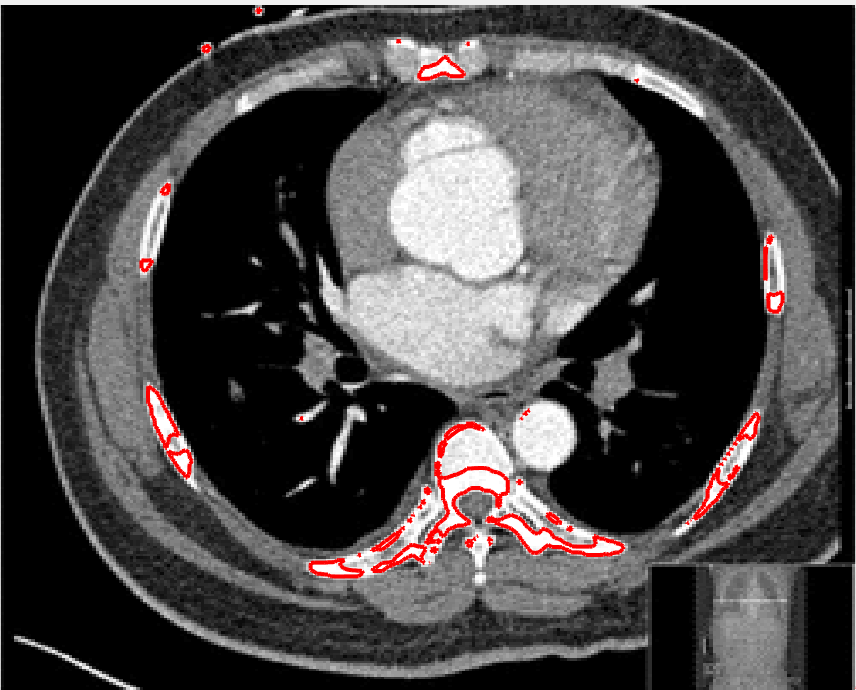

In Figure 2, each column shows an example for each of the problems listed above. We now propose solutions to each of these problems.

Refer to caption

Figure 2: Examples of images showing the problems discussed and the resulting geodesic distance maps. Column 111 shows the lack of robustness to noise, column 222 shows that outside the patient we have unreasonably low distance penalty, column 333 shows how the blurred edge under the aorta leads to the distance term being very low throughout the heart.